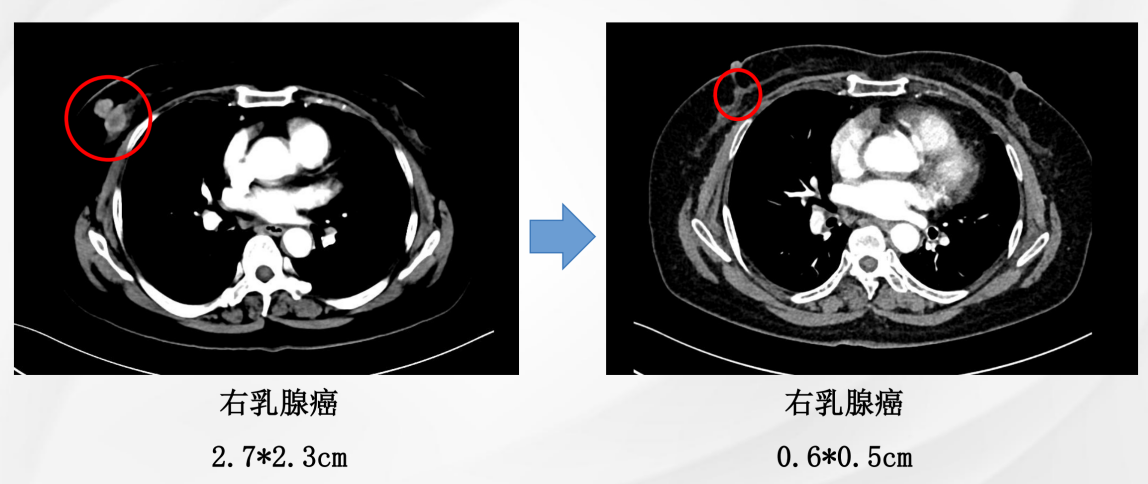

患者为女性,60岁,已绝经,既往史无特殊。2021年5月10日于院内行乳腺及淋巴结彩超检查,提示右乳腺实性结节(BI-RADS 4C级)及右腋下肿大淋巴结。进一步影像学评估显示,右乳原发灶大小约2.7×2.3 cm,右腋窝淋巴结约1.8×1.3 cm;同时可见双肺结节,最大约0.9×0.7 cm,并见右肺门淋巴结约1.1×1.0 cm。整体影像学结果提示患者初诊时已存在乳腺原发灶伴区域淋巴结及肺部转移。

图1:右乳腺肿物

治疗2个月后影像学复查结果示:右乳腺原发灶由2.7 × 2.3 cm缩小至2.4 × 2.1 cm;右腋窝淋巴结由1.8 × 1.3 cm缩小至1.3 × 0.9 cm;右肺中叶结节由0.9 × 0.7 cm缩小至0.7 × 0.6 cm;右肺门淋巴结由1.1 × 1.0 cm缩小至1.0 × 0.9 cm。本次复查显示乳腺原发灶缩小11%腋窝淋巴结、肺病灶、右肺门淋巴结均缩小。总体疗效评估为疾病稳定(SD)。这提示患者在治疗早期即出现客观影像学改善,但尚未达到部分缓解(PR)阈值。

截至治疗4年6个月时,患者仍维持持续获益。右乳腺原发灶缩小至0.6 × 0.5 cm;右腋窝淋巴结缩小至0.4 × 0.3 cm;右肺中叶原结节影未再显示;右肺门淋巴结缩小至0.7 × 0.4 cm。本次复查显示乳腺原发灶缩小78%;腋窝淋巴结、肺病灶、右肺门淋巴结影像学CR。总体疗效评估为持续PR。